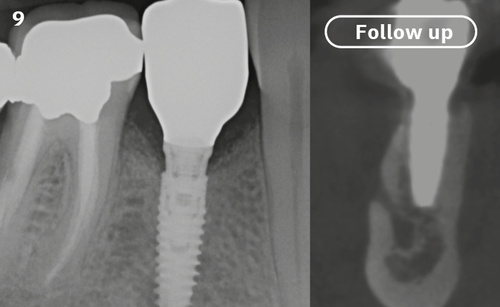

"After the extraction, I realized that the buccal wall was missing and I had to leave the membrane exposed. The regenerative potential of the site could be poor, so I decided to boost the biomaterials’ effect with polynucleotides and hyaluronic acid."

The Situation

The patient (45 years old, female, non-smoker, no previous pathologies) is referred for extraction of tooth 45 and immediate implant placement. The site showed an increased probing depth and a marked bone loss.